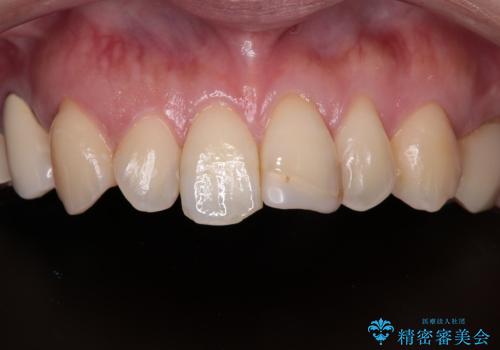

- 以前保険診療で行った前歯を自然できれいなセラミックにしたいと来院された患者様です。

古い材料と虫歯を除去して、土台の形を整え、より自然なオールセラミッククラウンにすることとしました。

セラミックは噛み合わせによっては欠けてしまうことがあるため、その予防でナイトガードを製作しました。